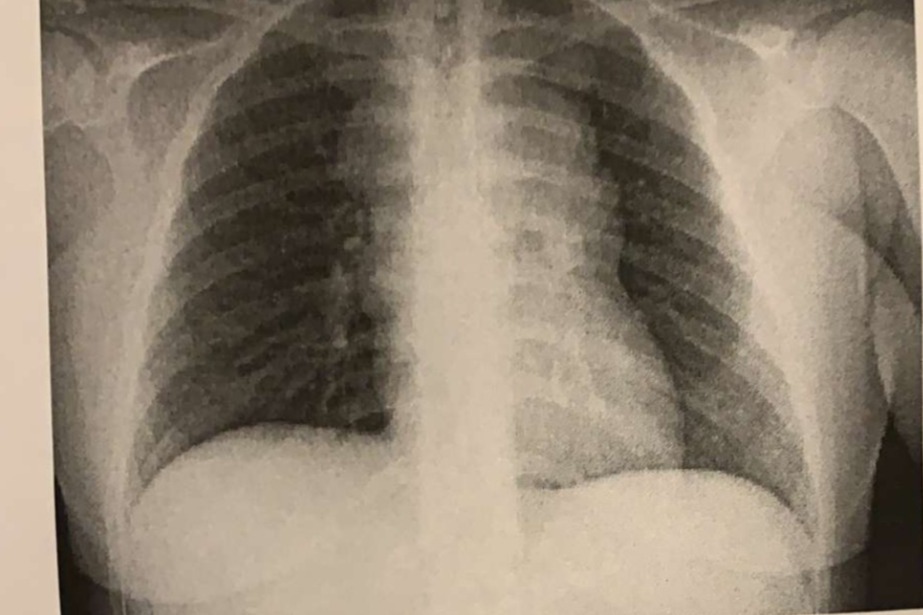

HELP OLIVIA (15) OVERCOME STAGE 2 HODGKIN'S LYMPHOMA RIGHT ABOVE HER HEART. INOPERABLE.

Growing up Olivia was very energetic and outgoing. She was always ready to tackle any new obstacles that came her way, or help others tackle theirs. My mom really had her hands full with us, It really took a village… Our mom is now disabled though, Olivia has now been helping out her family at home. On March 2nd 2021 Olivia got diagnosed with rare stage 2 Hodgkin's lymphoma.